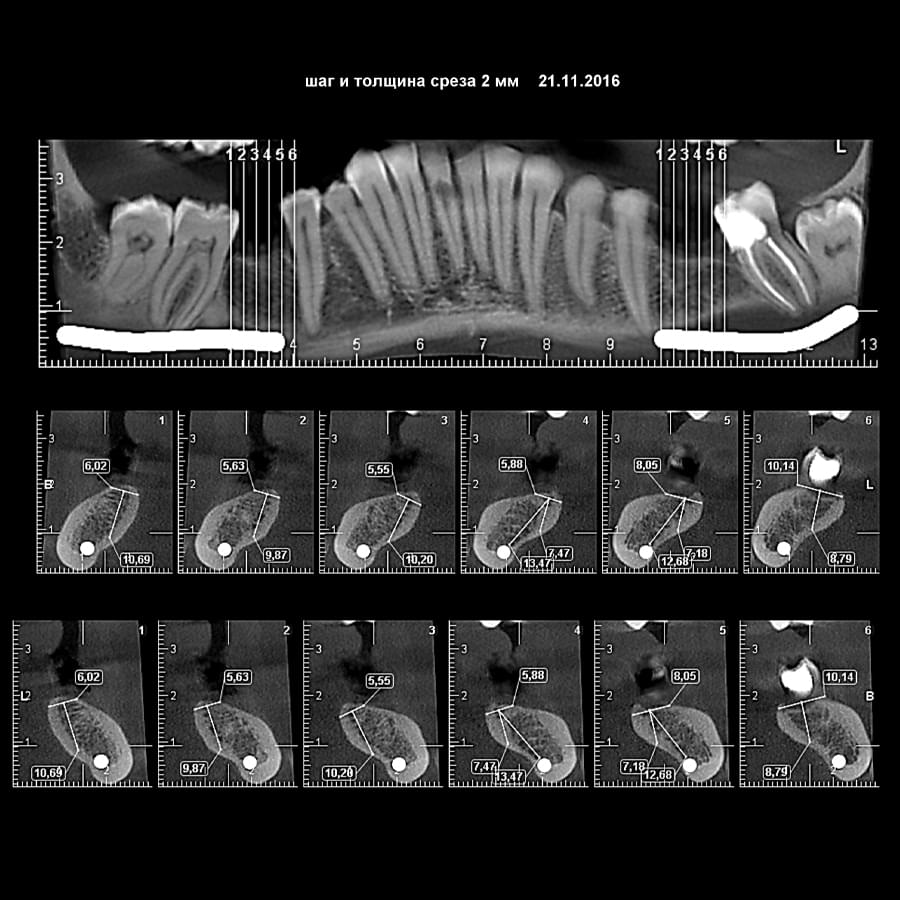

Успішна імплантація починається з бездоганної діагностики. Томограф PLANMECA забезпечує

зображення в реальному масштабі 1:1 без геометричних спотворень, що критично важливо для

вибору розміру та позиції імплантату.

Ми економимо ваш час, надаючи повний пакет передопераційної підготовки:

Детальна розмітка: промальовування нижньощелепного каналу, візуалізація синусів та

ментальних отворів.

Точні виміри: визначення висоти та ширини альвеолярного гребеня, а також оцінка щільності

кісткової тканини в зоні майбутньої операції.